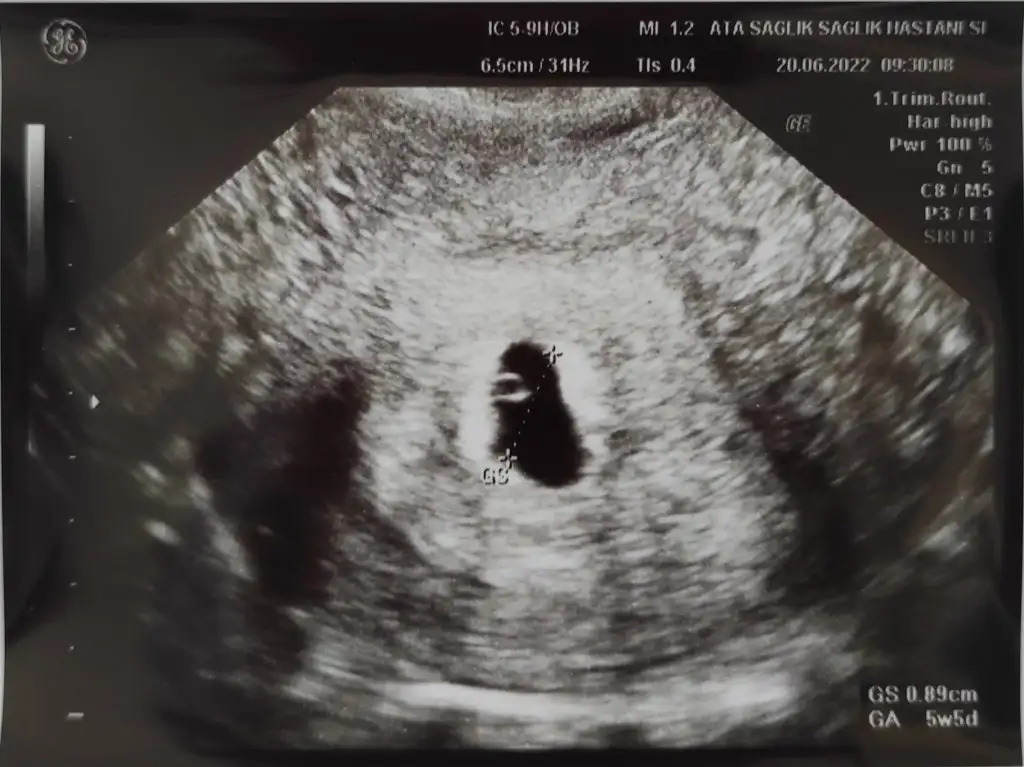

Merhaba canım benimkinide tahmin edebilir misin rica etsem 5+5 teyim şuan karından ultrosanla çekindimSelam Kızlarbir çok kişi gruplardan beni bilir. Yine yetiştim imdatlara